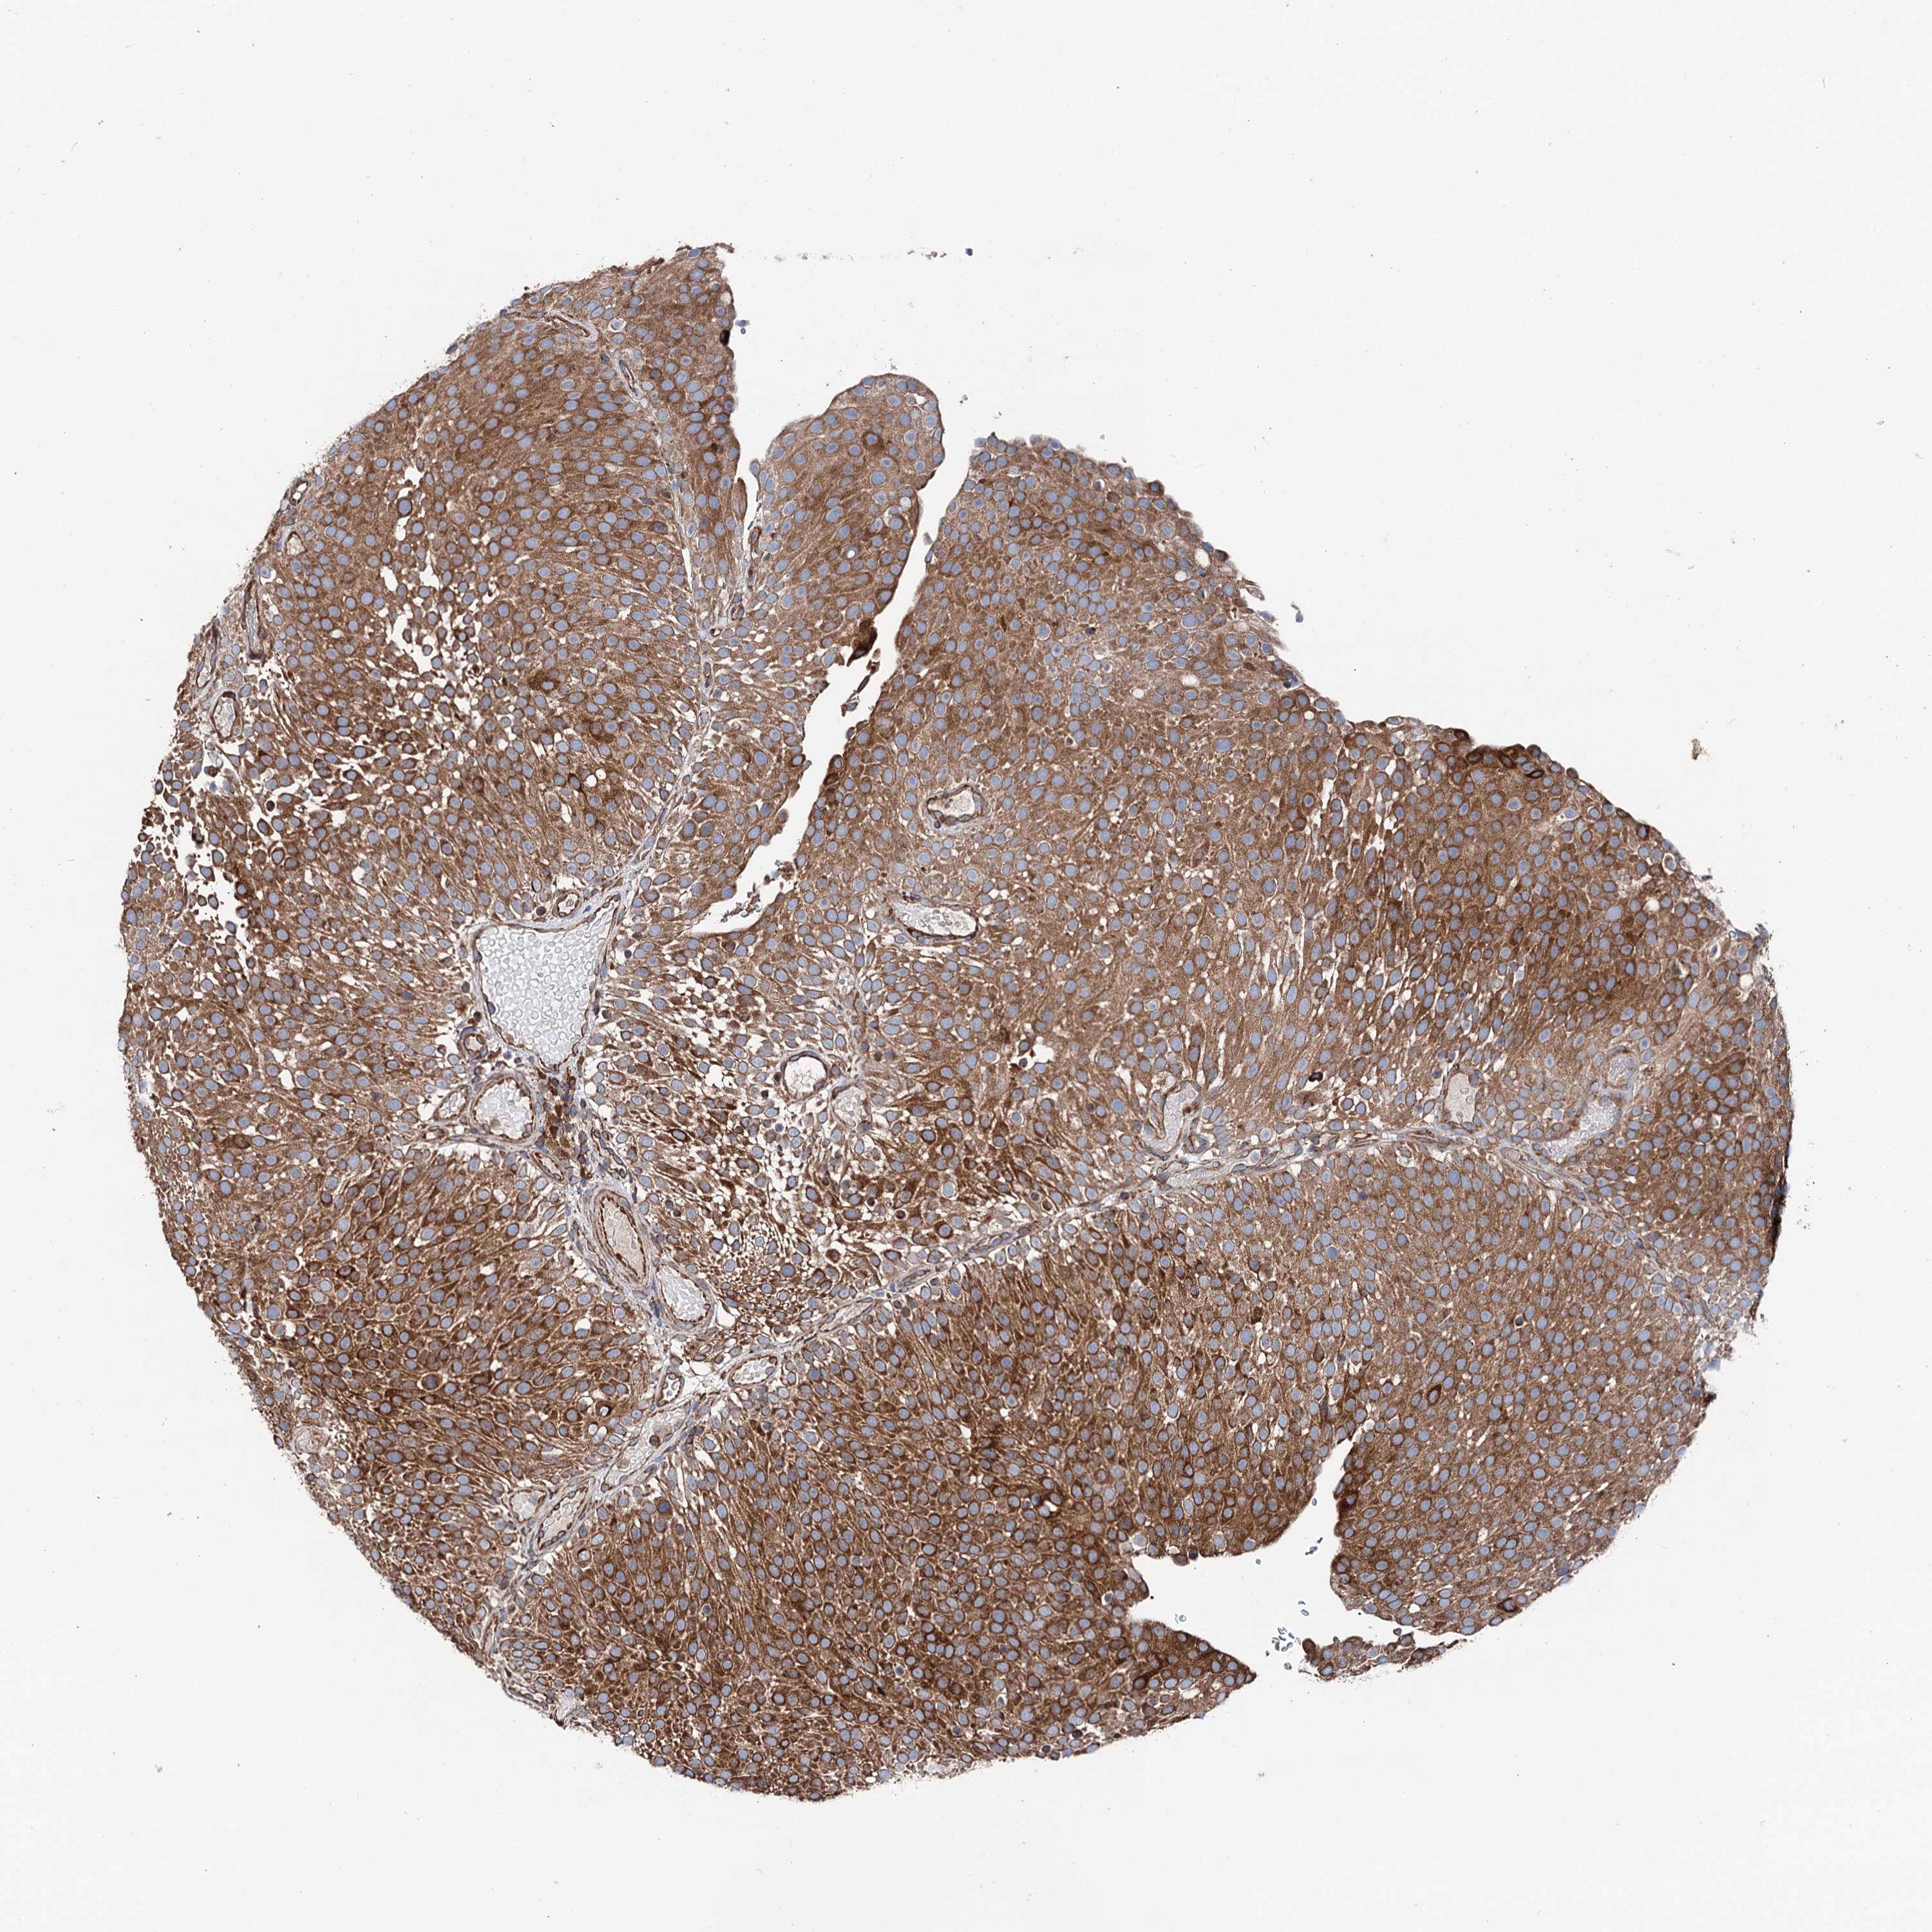

UROTHELIAL CANCER - Protein expressioni

A mouse-over function shows sample information and annotation data. Click on an image to view it in a full screen mode. Samples can be filtered based on level of antibody staining by selecting one or several of the following categories: high, medium, low and not detected. The assay and annotation is described here.

Note that samples used for immunohistochemistry by the Human Protein Atlas do not correspond to samples in the TCGA dataset.

Antibody stainingi

Antibody staining in the annotated cell types in the current human tissue is reported as not detected, low, medium, or high, based on conventional immunohistochemistry profiling in selected tissues. This score is based on the combination of the staining intensity and fraction of stained cells.

Each image is clickable and will lead to virtual microscopy that enables deeper exploration of all samples and also displays staining intensity scores, fraction scores and subcellular localization as well as patient and tissue information for each sample.

Antibody HPA039363

Antibody HPA039456

Staining

High

Medium

Low

Not detected

Intensity

Strong

Moderate

Weak

Negative

Quantity

>75%

75%-25%

<25%

None

Location

Nuclear

Cytoplasmic/membranous

Cytoplasmic/membranous,nuclear

Urothelial carcinoma, High grade

Urothelial carcinoma, Low grade

Urothelial carcinoma, NOS